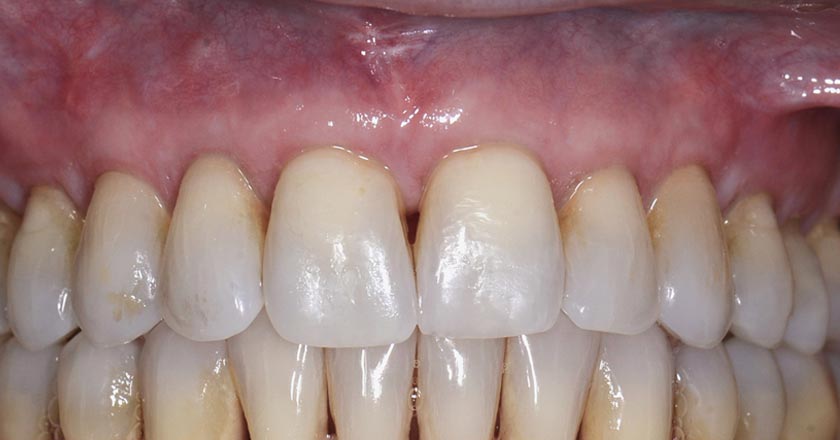

Gum Disease - Before And After